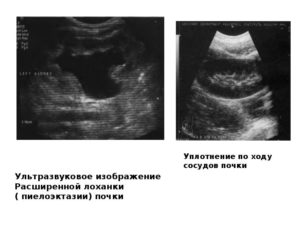

Достаточно часто термин «уплотнение ЧЛС почек » можно встретить в заключениях врачей ультразвуковой диагностики.

В действительности, уплотнение ЧЛС одной или обеих почек — только ультразвуковой критерий, указывающий на повышение плотности ткани, которая хуже пропускает ультразвуковые волны.

На УЗИ признаки уплотнения можно увидеть, начиная со второй стадии воспаления, в третьей они становятся еще более выраженными.

Чашелоханочная система окружена фиброзной и жировой тканью, кровеносными и лимфатическими сосудами. Все вместе они образуют анатомическую структуру, которая называется почечным синусом.

Если УЗИ проводится натощак, то в норме врач может увидеть только почечный синус целиком. Выделить из него ЧЛС невозможно.

При исследовании с водной нагрузкой чашечки и лоханки становятся видны и выглядят как древовидное образование.

В норме чашелоханочная система уплотнена у детей до трех лет и людей старше 60 лет. У детей все структуры почки, включая чашечки и лоханку, располагаются более компактно, чем у взрослых. У лиц пожилого возраста наблюдаются начальные признаки склероза собирательной системы и сосудов, поэтому почечный синус выглядит более плотным.